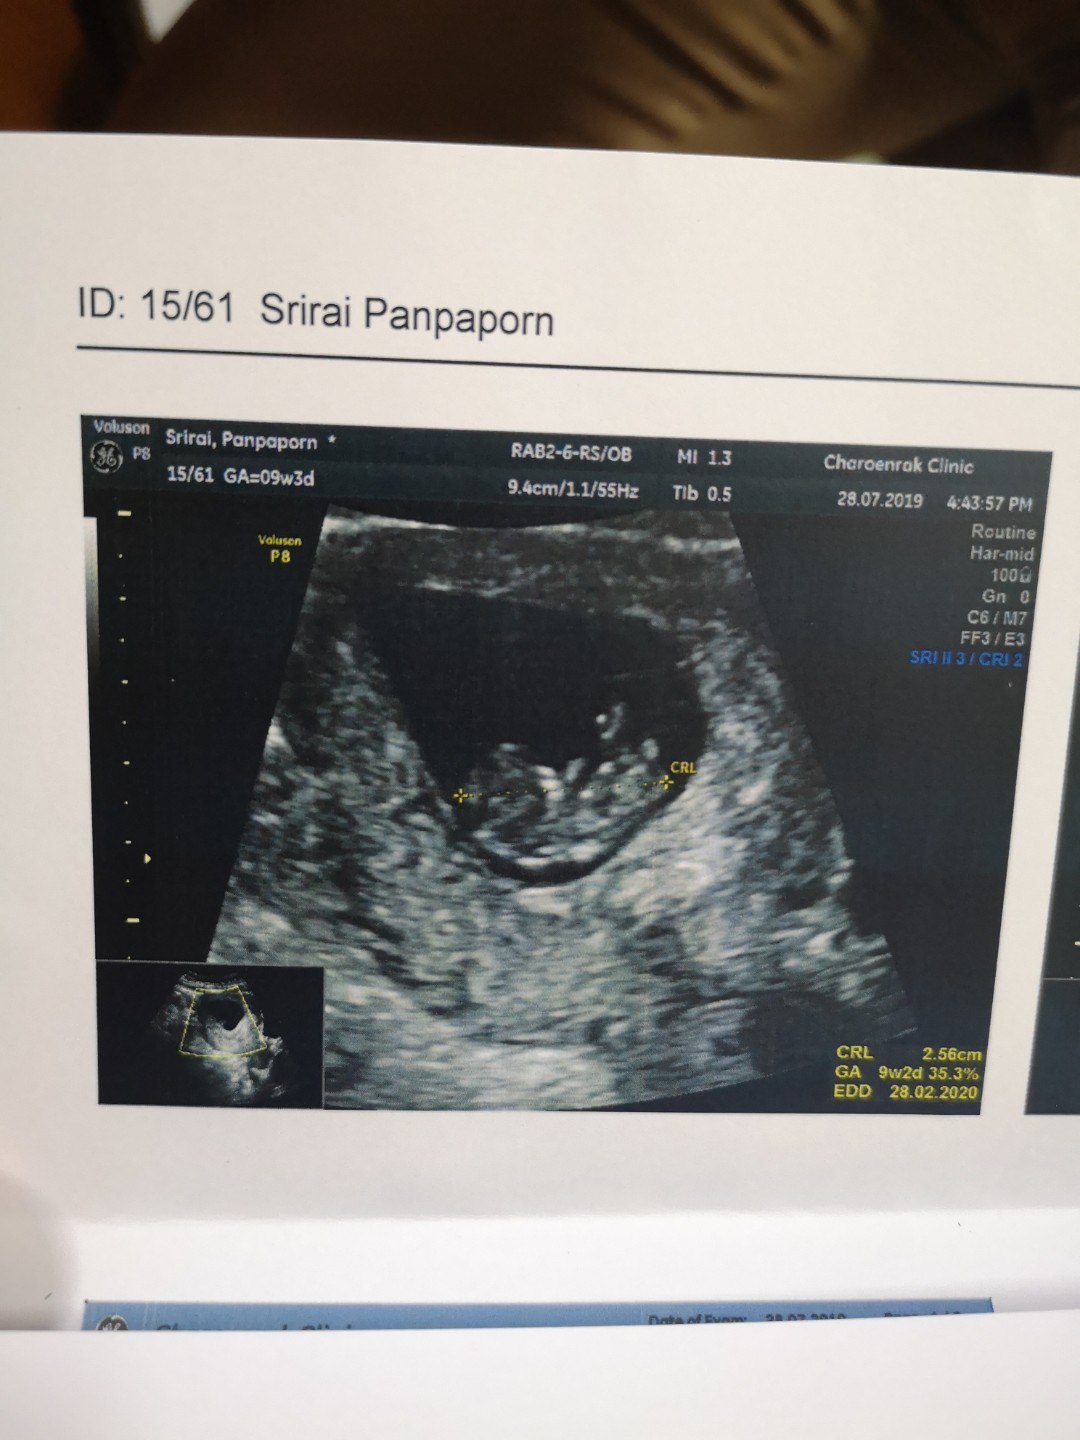

9w ค่ะ

VIP Member